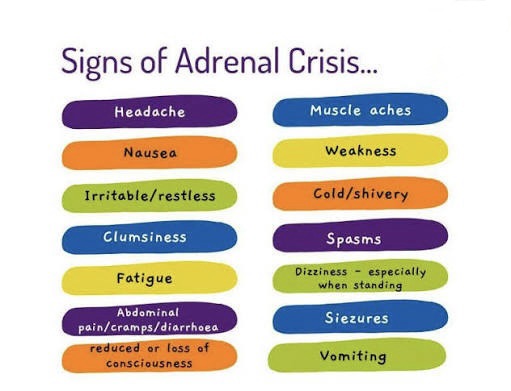

When Your Body Runs on Empty: Understanding Low Cortisol After Immunotherapy

When Fitness Changes Overnight: Living and Exercising with Immune-Related Adrenal Insufficiency

Living with not just cancer but “adrenal insufficiency” thrown in for fun.

Immunotherapy and Adrenal Insufficiency: When Treatment Saves You… But Changes You